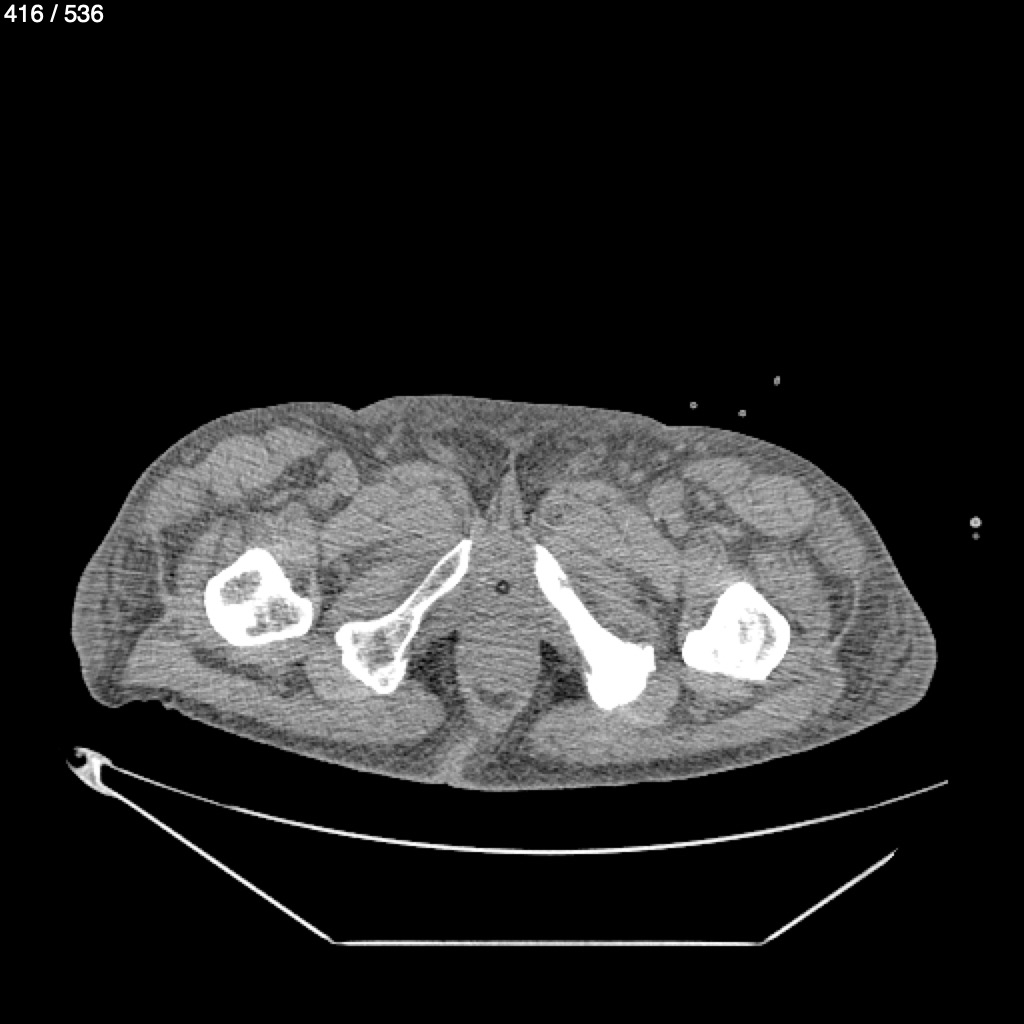

Angel Villalobos Palomeque 73 A - T.C Abdomen Simple